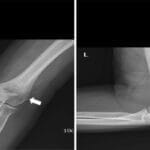

In some cases, bone support with plates, screws, or other hardware may be necessary.

Post-surgery, patients may require splints, casts, slings, or braces to aid in recovery.

Wide resection often necessitates bone reconstruction using donor bone (allograft) or artificial implants, such as metal bone replacements.